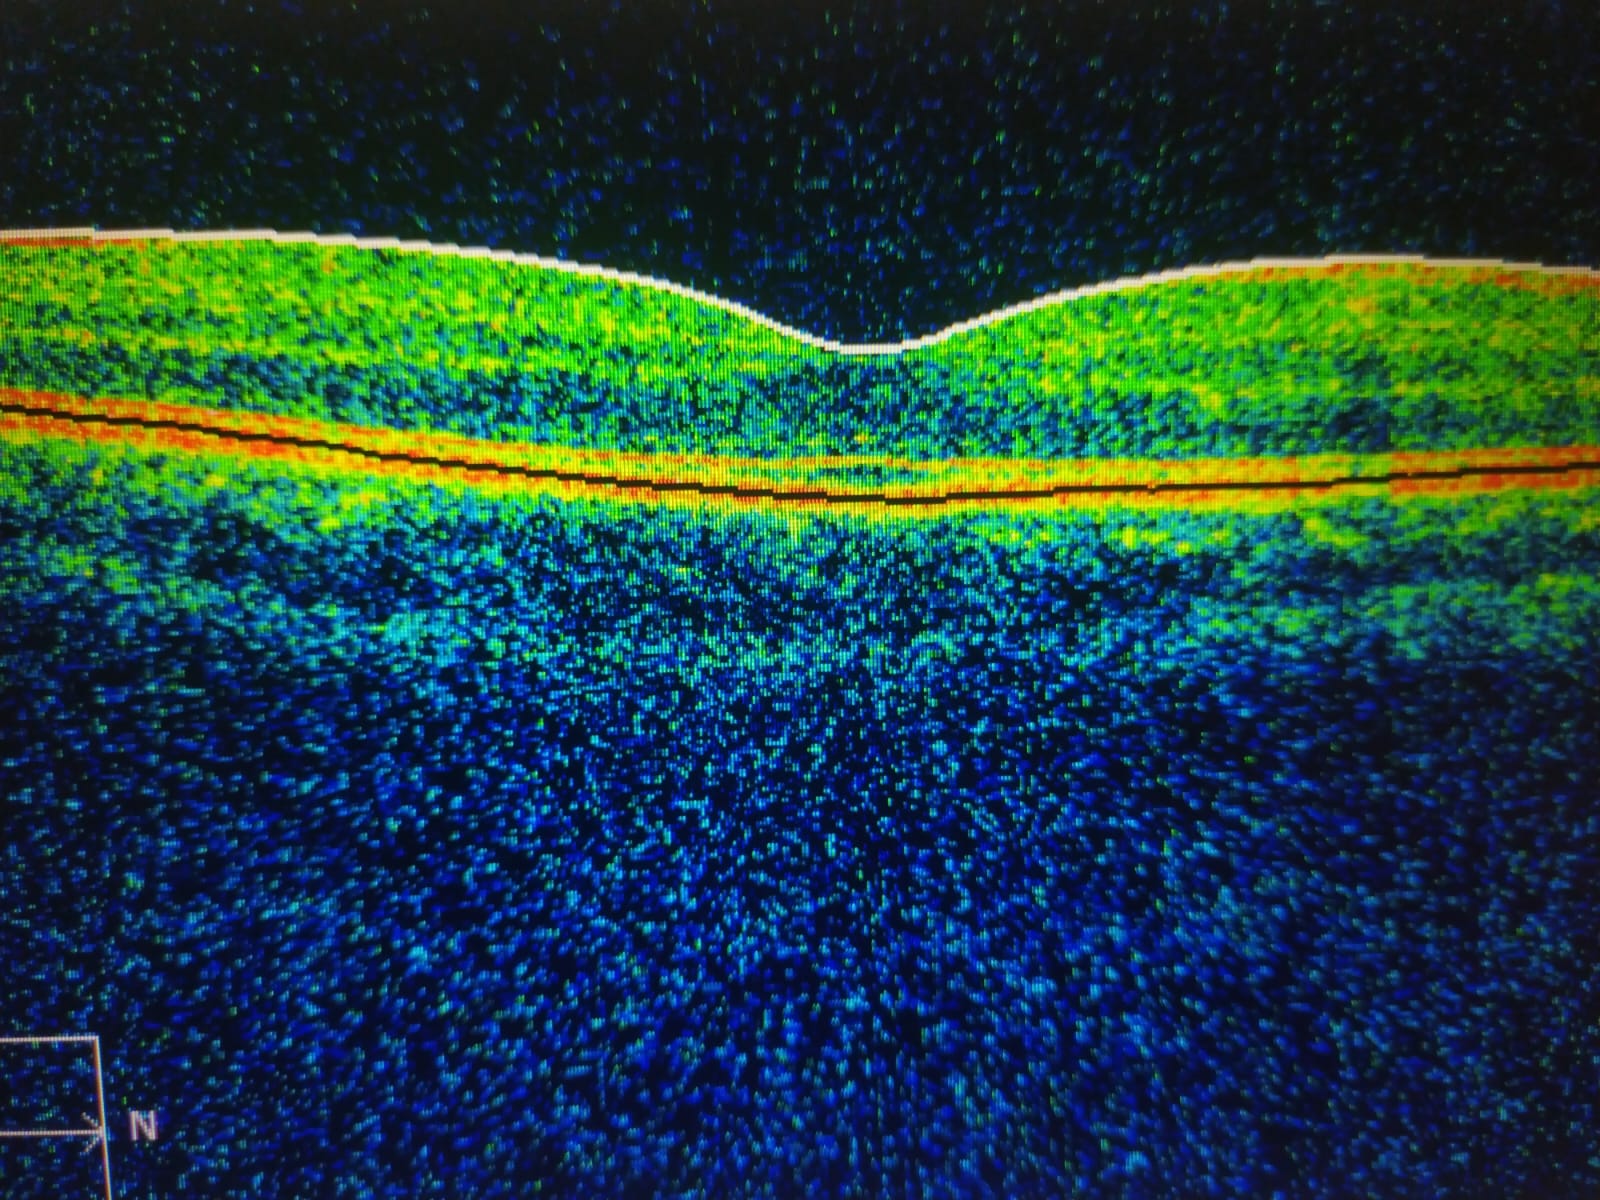

- OCT: Tomografía de coherencia óptica de mácula, disco y fibras nerviosas